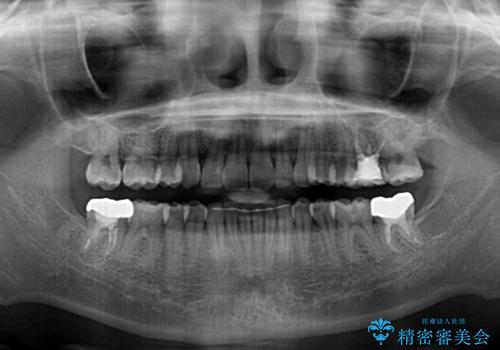

- 上顎の重なっている前歯を気にして来院された患者様です。

八重歯改善には抜歯が必要で、八重歯の移動量が多く、更には右側にずれている正中を改善する必要がありました。

インビザライン単体での治療は困難と判断し、補助装置により八重歯移動後にインビザラインを用いることとしました。

インビザラインでは治療期間が延びることが予想されたため、ワイヤー矯正を提案しましたが、セラミッククラウンが多く、壊すあるいは傷が付く可能性があることから、長期間であってもインビザラインを選択されました。